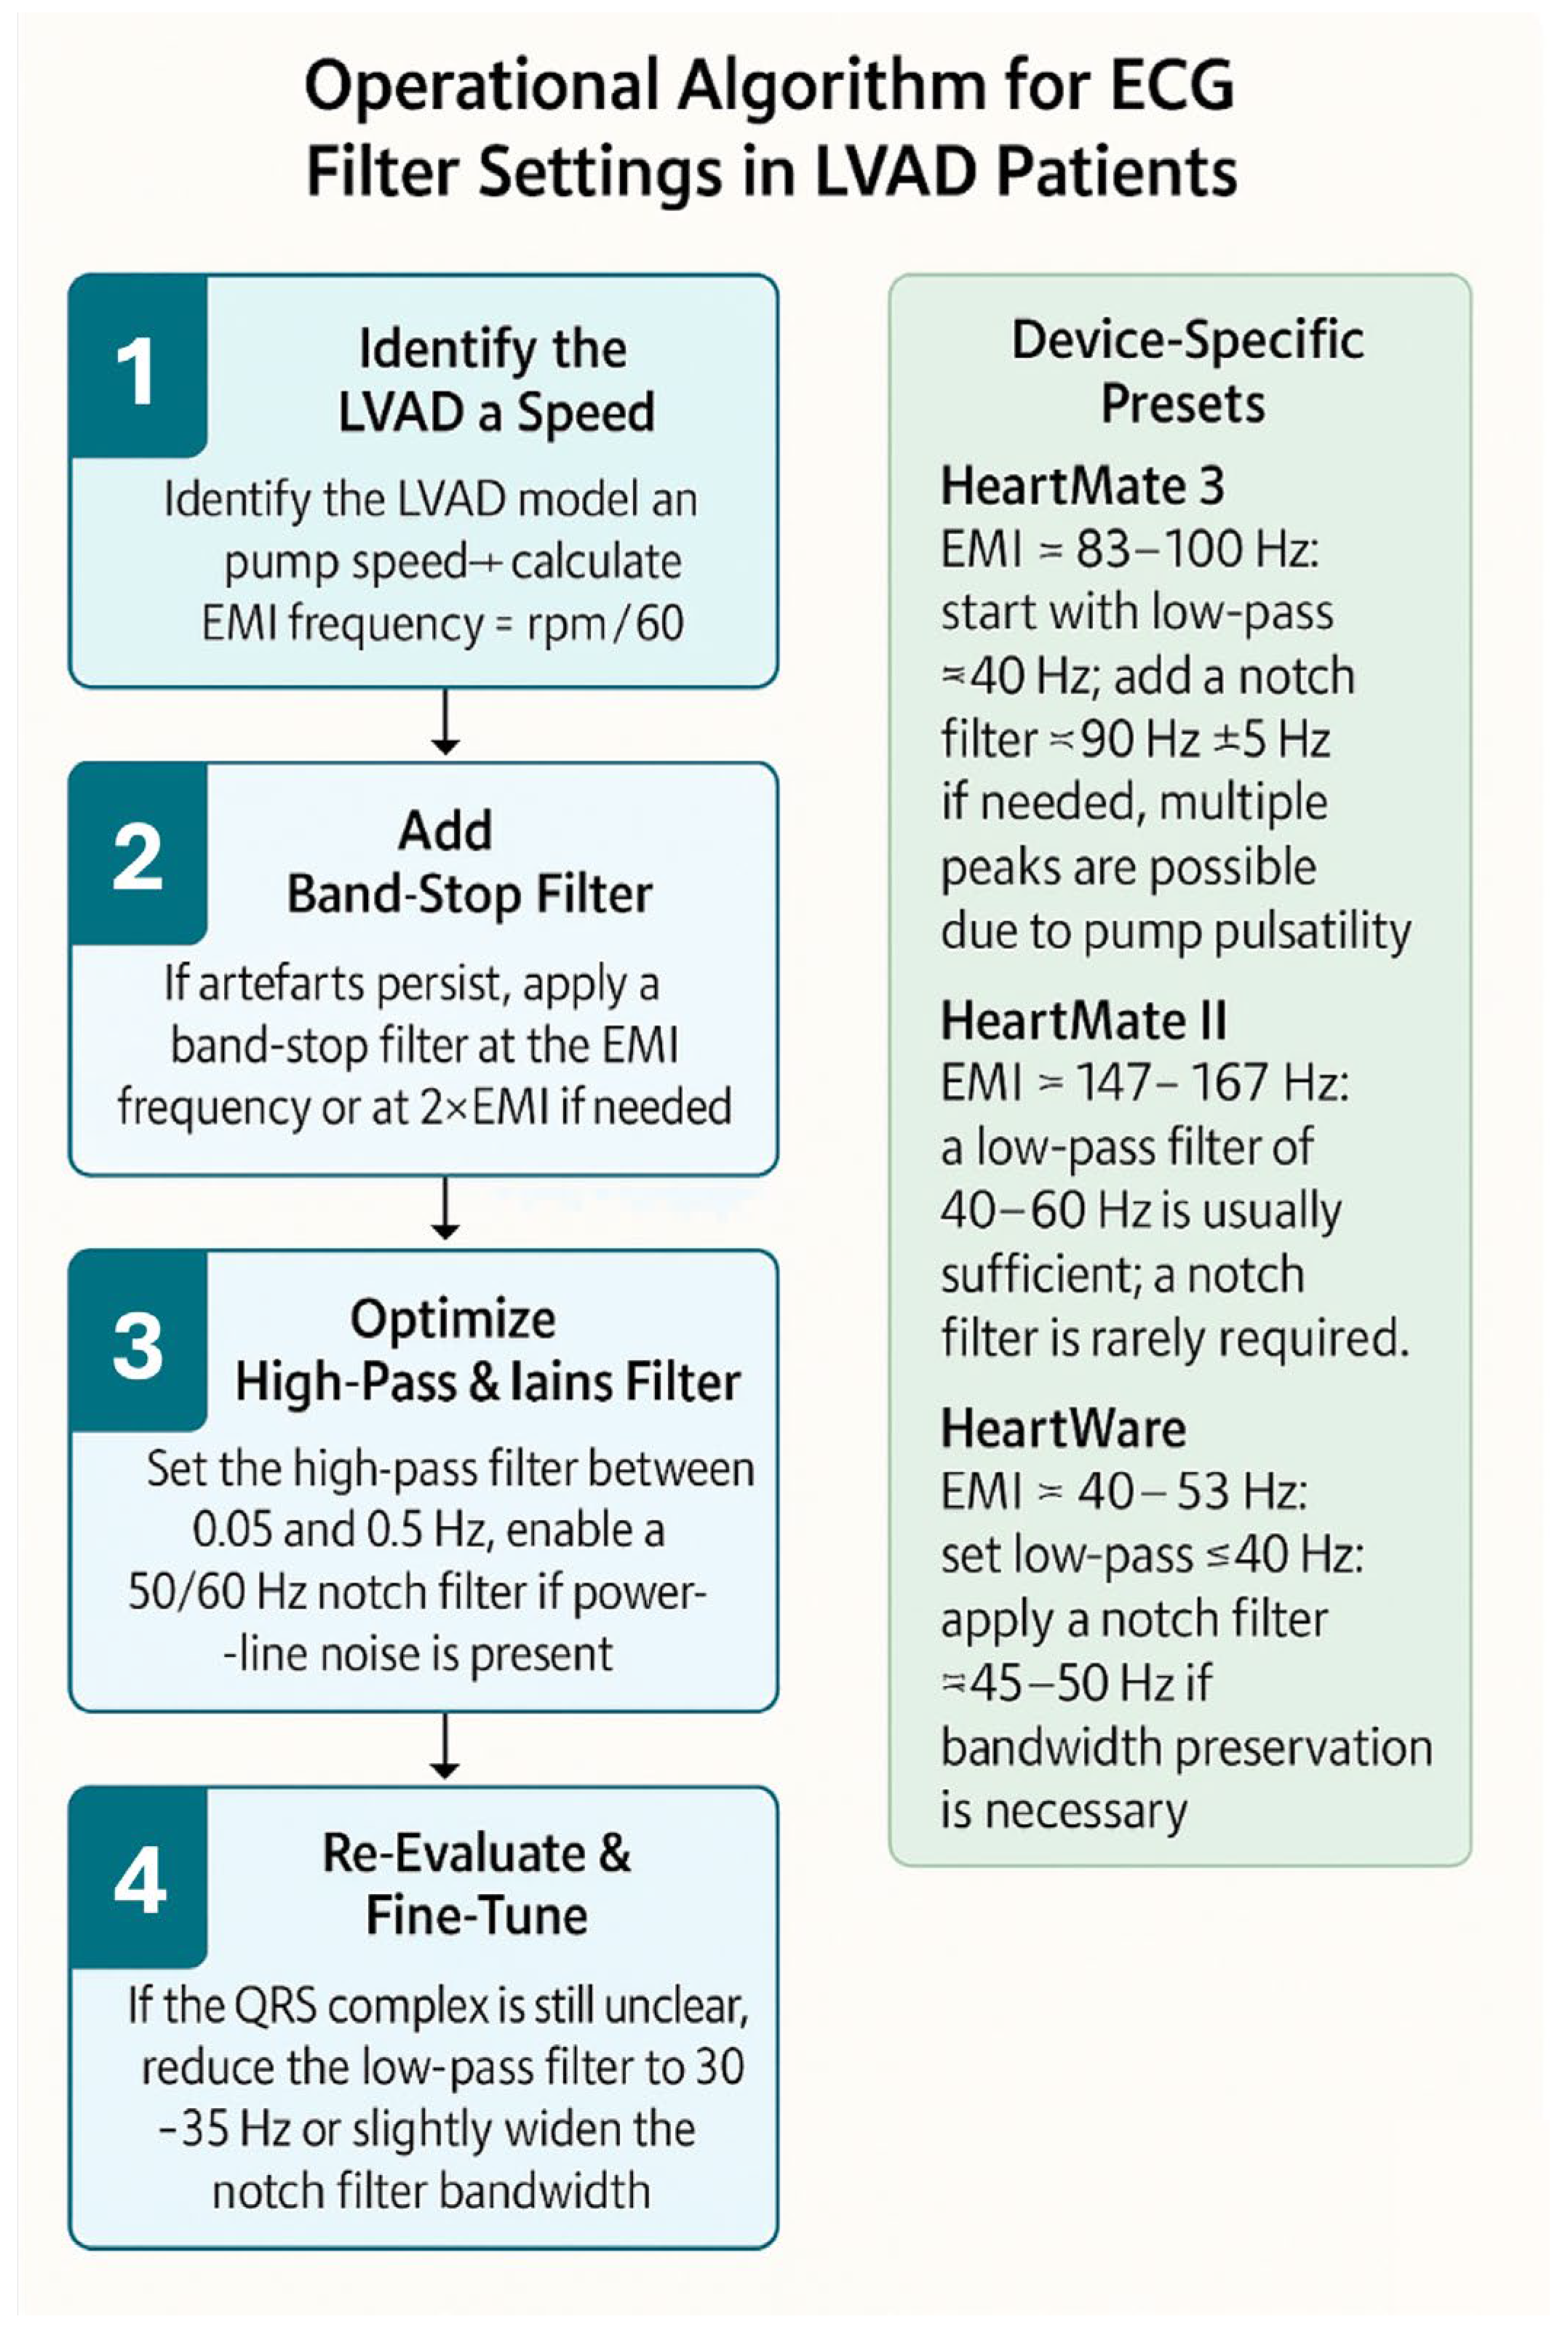

| LVAD Model | Typical Pump Speed(rpm) | Main EMI Frequency (Hz) | Recommended Low-Pass Filter | Band-Stop Filter Option | Notes/Tips |

|---|---|---|---|---|---|

| HeartMate 3 (Abbott) | 5000–6000 rpm | ~83–100 Hz | Set low-pass ≈40 Hz; preserves QRS morphology but may attenuate ST segments | Band-stop at pump-specific peak (~83–100 Hz) | Multiple peaks may occur due to the pump’s artificial pulsatility; more than one notch filter may be required |

| HeartMate II (Abbott) | 8800–10,000 rpm | ~147–167 Hz | Low-pass 40–60 Hz usually sufficient; artefact occurs at high frequencies | Notch filter rarely needed unless peaks overlap power-line frequency | High-frequency artefacts; lowering the low-pass filter to ≈40 Hz almost always improves ECG clarity |

| HeartWare (Medtronic) | 2400–3200 rpm | ~40–53 Hz | Set low-pass ≤40 Hz to suppress primary artefact | Optional: notch filter around 40–50 Hz | Artefacts usually occur at lower frequencies and are easily managed by lowering the low-pass filter |